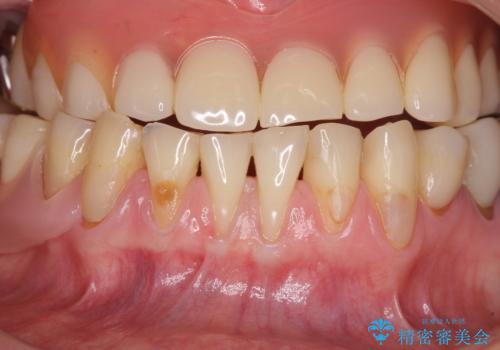

- 咬み合わせにより下の前歯の歯肉が退縮してしまい、根が見えていることが気になるとのことで来院された患者様です。

歯肉退縮に対して、上顎からの結合組織移植術(CTG)により、歯根の被覆を行うとともに、歯肉の厚みを増すことで将来の退縮リスクを抑制することとしました。

歯肉が大変薄かったため、歯肉移植による根面被覆の効果はそれほど高くないように思われましたが、想像以上に歯肉の位置を回復させることができました。

歯肉の厚みも十分に獲得でき、患者様には大変満足していただきました。